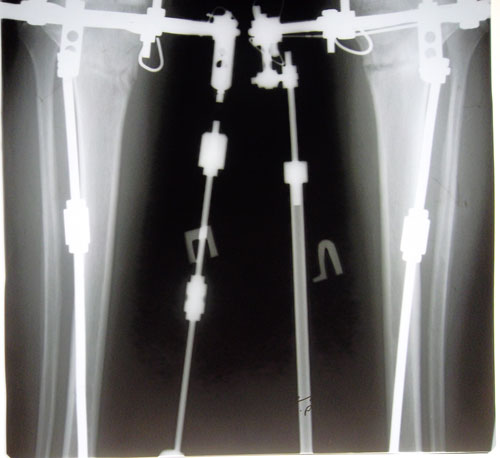

- Диагноз: О-образная деформация ног

поздравляю ножки получаются загляденье, стала замечать что ноги которые "делал" Н.Н. намного привлекательнее чем у тех кто имел от природы ровные ноги